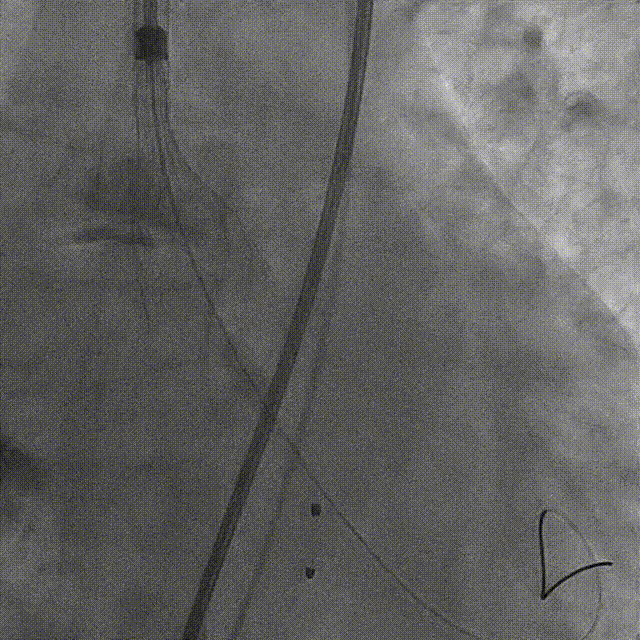

术中采用局麻强化策略,使用右侧股动脉入路,成功穿刺后,首先置入20 F大鞘,并于大鞘中置入一个5 F鞘管和一个10 F鞘馆。使用10 F鞘馆送入导丝,成功完成跨瓣操作,并使用5 F鞘管送入猪尾导管到达主动脉根部。随后沿导丝送入20 mm球囊,180次/min快速起搏下行球囊预扩张,同时进行主动脉根部造影,造影结果显示,预扩球囊腰征明显,无瓣周漏,冠脉亦未受影响,可以选择TaurusElite 23 mm可回收瓣膜。

明确植入瓣膜尺寸后,由于是单血管入路,因此先撤出猪尾导管,再送入TaurusElite可回收瓣膜输送系统,当输送系统到达降主动脉后,再次使用5 F鞘管送入猪尾导管于主动脉瓣根部,并继续将输送系统送到主动脉瓣处,顺利跨瓣。

首次释放瓣膜尝试零位释放,当瓣膜释放到一半时行主动脉根部造影,发现瓣膜释放位置偏低,遂回收瓣膜重新定位后再次释放,当瓣膜释放一半时再行主动脉根部造影,发现瓣膜位置良好,遂完全释放瓣膜。